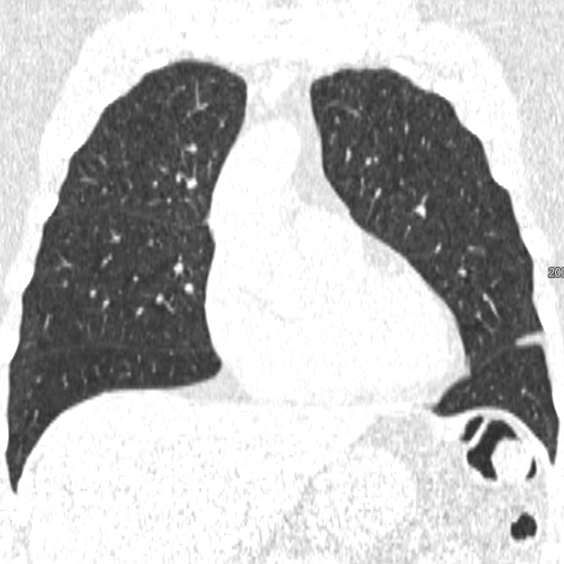

We applied the described segmentation pipeline to the 14 testing datasets which were not used for training and validation. Segmentation including postprocessing takes less than 6 seconds for a case. We compared our method to two other approaches: 1. a non-deep-learning-based automatic method [Lassen et al.(2013)Lassen, van Rikxoort, Schmidt, Kerkstra, van Ginneken, and Kuhnigk] 2. the same u-net as proposed but without weighting. The mean distance from the visible fissure improved to 1.46 mm (without weighting: 2.08 mm). See Figure 2 for plots and Figure 3 for screenshots.

We trained a 3D u-net for a lung lobe segmentation task and showed that emphasizing the lobar boundaries in the loss function improved the segmentation results (see Figure 2 and 3). The segmentation quality is comparable to the method proposed in [Lassen et al.(2013)Lassen, van Rikxoort, Schmidt, Kerkstra, van Ginneken, and Kuhnigk] and even slightly better for the left lobes. This study was performed on a small amount of data. In future work, we plan to train with the same architecture on a much larger database including a wide range of pathologies and performing an extensive evaluation with participation in the LOLA11 [LOLA11()] challenge.